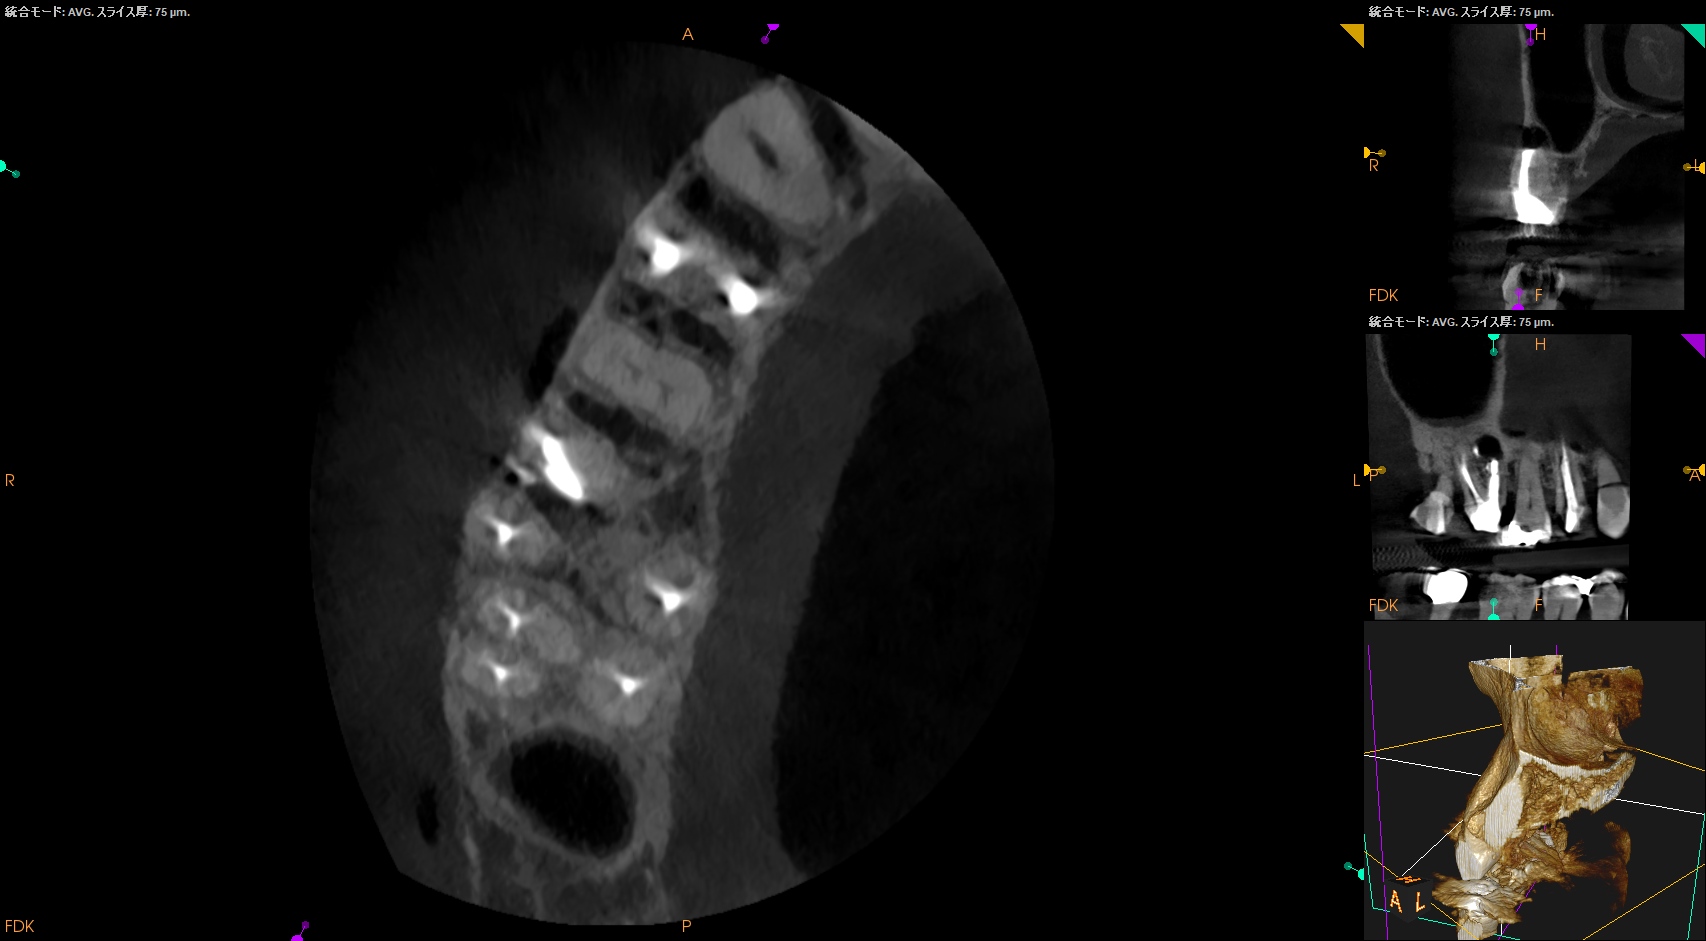

紹介患者さんの治療で、#3 MB Apicoectomyを行ったのだが

その際は、この穿孔部を消去したいので

さらに切断部位から4mm, 頬舌的幅径が6.7mm必要だが再切断し逆根管形成・充填を試みることにした。

人為的にApico-marginal deffectを作らないように注意する必要があるだろう。

再切断したら…

Apico-marginal deffectを人為的に作成してしまった。

ここで一気にテンションが下がるが、以下のように終わらせた。